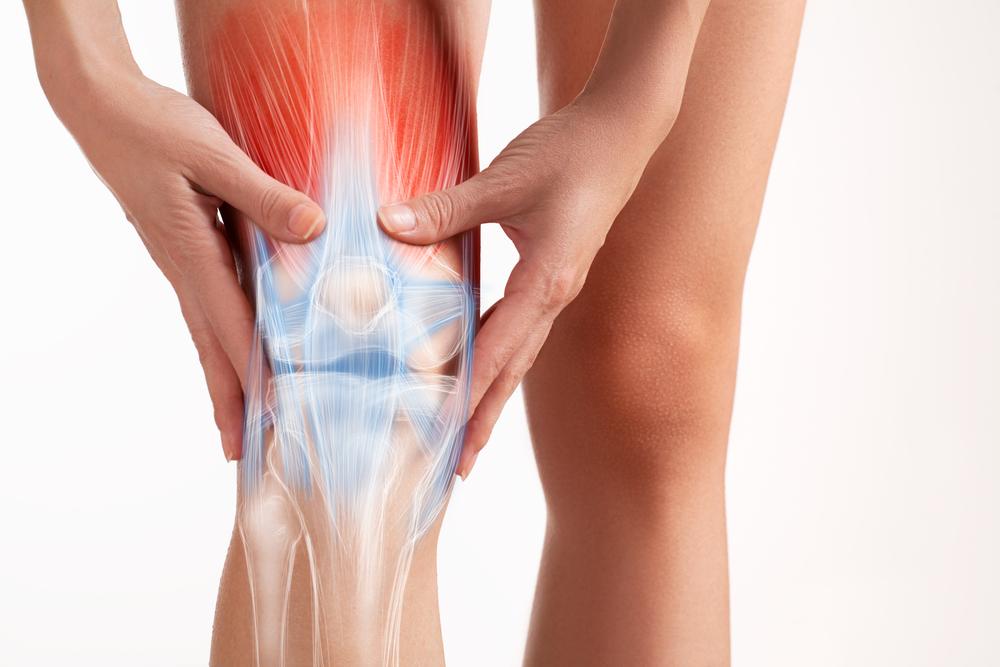

အဆစ်ရောင်နာ (Arthritis)

အဆစ်ရောင်နာ (Arthritis) ဆိုတာ အဆစ်တွေကို ထိခိုက်စေနိုင်တဲ့ ကျန်းမာရေးပြဿနာ တစ်မျိုးပါ။ အဆစ်တွေ နာကျင်တာ၊ ရောင်ရမ်းတာတွေ ဖြစ်စေနိုင်ပါတယ်။ လှုပ်ရှားဖို့ ခက်တာ၊ တက်တက်ကြွကြွနေဖို့ ခက်တာမျိုးတွေကိုလည်း ခံစားရနိုင်ပါတယ်။ အဆစ်ရောင်နာတွေက အမျိုးမျိုးပါပဲ။ တစ်မျိုးစီတိုင်းမှာ မတူညီတဲ့ လက္ခဏာတွေ ခံစားရနိုင်ပါတယ်။ အဆစ်ရောင်နာ အမျိုးအစားကို လိုက်ပြီး ကုထုံးတွေလည်း ကွာခြားနိုင်ပါတယ်။ အဆစ်ရောင်နာ က များသောအားဖြင့် အသက်အရွယ် ကြီးရင့်သူတွေမှာ အဖြစ်များပါတယ်။ အမျိုးသားတွေမှာ ဖြစ်နိုင်သလို အမျိုးသမီးတွေ၊ ကလေးတွေမှာလည်း ဖြစ်နိုင်ပါတယ်။ အရွယ်သုံးပါးစလုံး ခံစားရနိုင်တဲ့ ကျန်းမာရေး ပြဿနာပါ။ အဆစ်ရောင်နာ (Arthritis) ဆိုတာ အဆစ်ရောင်နာ ဆိုတာ အဆစ်တွေ ( အရိုး တစ်ခုခုနဲ့ တစ်ခု ဆုံပြီး လှုပ်ရှားမှုတွေ လုပ်ဆောင်နိုင်တဲ့ နေရာ) မှာ ထိခိုက်စေတဲ့ ကျန်းမာရေး […]